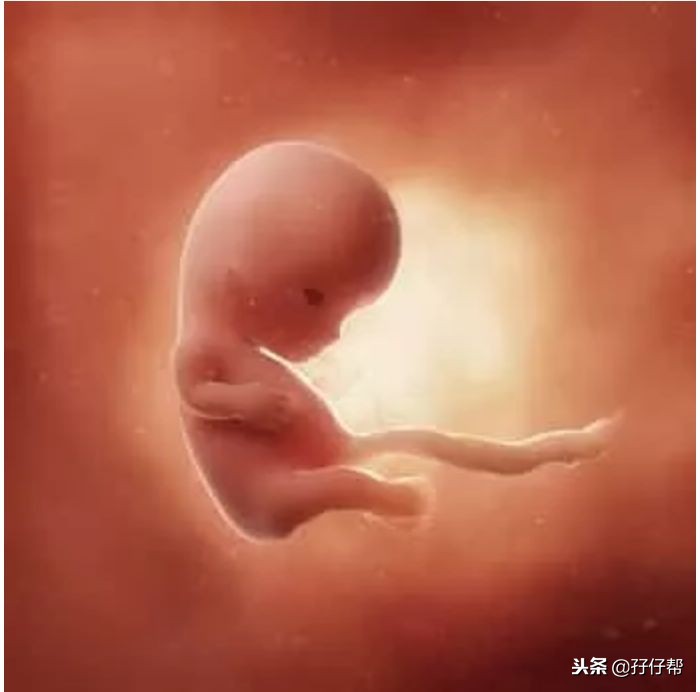

孕10周的胎宝宝,大概金桔般大小。从头到臀部长3.4CM 体重约8.5G,如图所示⏬⏬:

孕10周的双胞胎胎儿发育图⏬⏬: